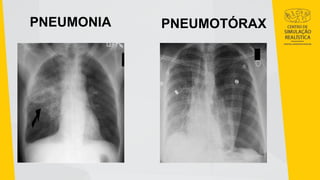

PNEUMONIA PNEUMOTÓRAX